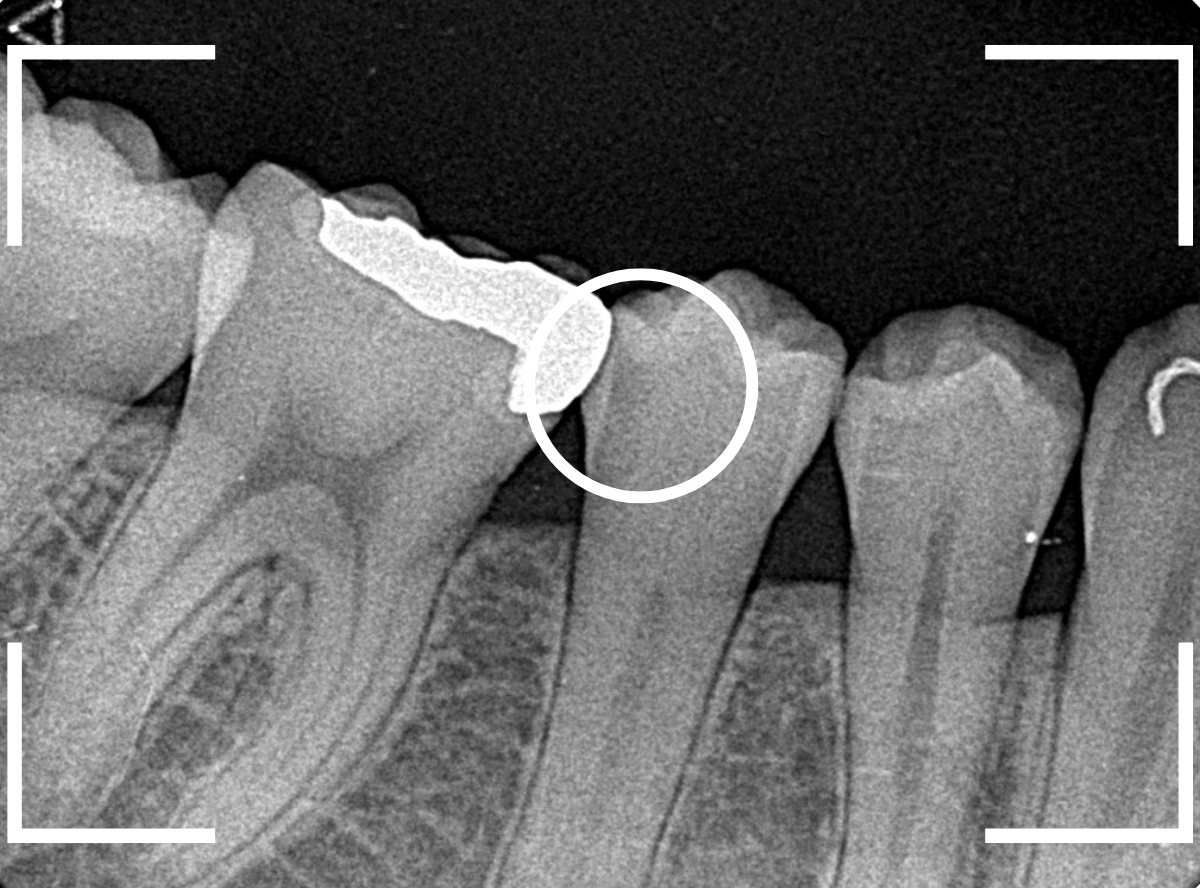

レントゲン写真で確認します。

金属のつめものの下が、神経まで達する大きな虫歯になっています。